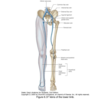

Pelvis bony anatomy

Deep muscles of gluteal region

Origin and insertion of piriformis

Anterior surface of sacrum

Greater trochanter

Origin and insertion of obturator internus

Internal surface of obturator foramen

Greater trochanter

Gluteus minimus origin and insertion

Inferior and anterior gluteal lines

Greater trochanter

Gluteus medius origin and insertion

Anterior and posterior gluteal lines

Greater trochanter

Gluteal maximus origin and insertion

Posterior gluteal line/ fascia covering gluteus medius

iliotibial tract of fascia lata and gluteal tuberosity